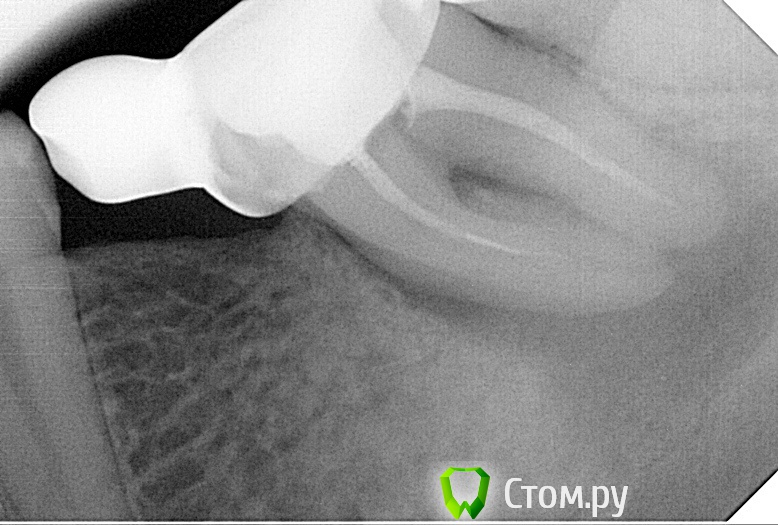

SanderS Опубликовано 28 октября, 2014 Поделиться Опубликовано 28 октября, 2014 (изменено) Пришла пациентка, жалобы на периодически ноющие боли слева НЧ, немного подвижен мост 3.7-3.8. Прогноз? Мосту 4 года, кармана по медиальной стенке не нащупал Изменено 28 октября, 2014 пользователем SanderS Ссылка на комментарий

SanderS Опубликовано 28 октября, 2014 Автор Поделиться Опубликовано 28 октября, 2014 Убрать консоль,эндо,полугодичный рекол.Ну собственно я так пациентке и сказал. Шеф сказал там киста ( смотри размеры!!!) - удалять, не в первый раз мнения расходятся. Ссылка на комментарий